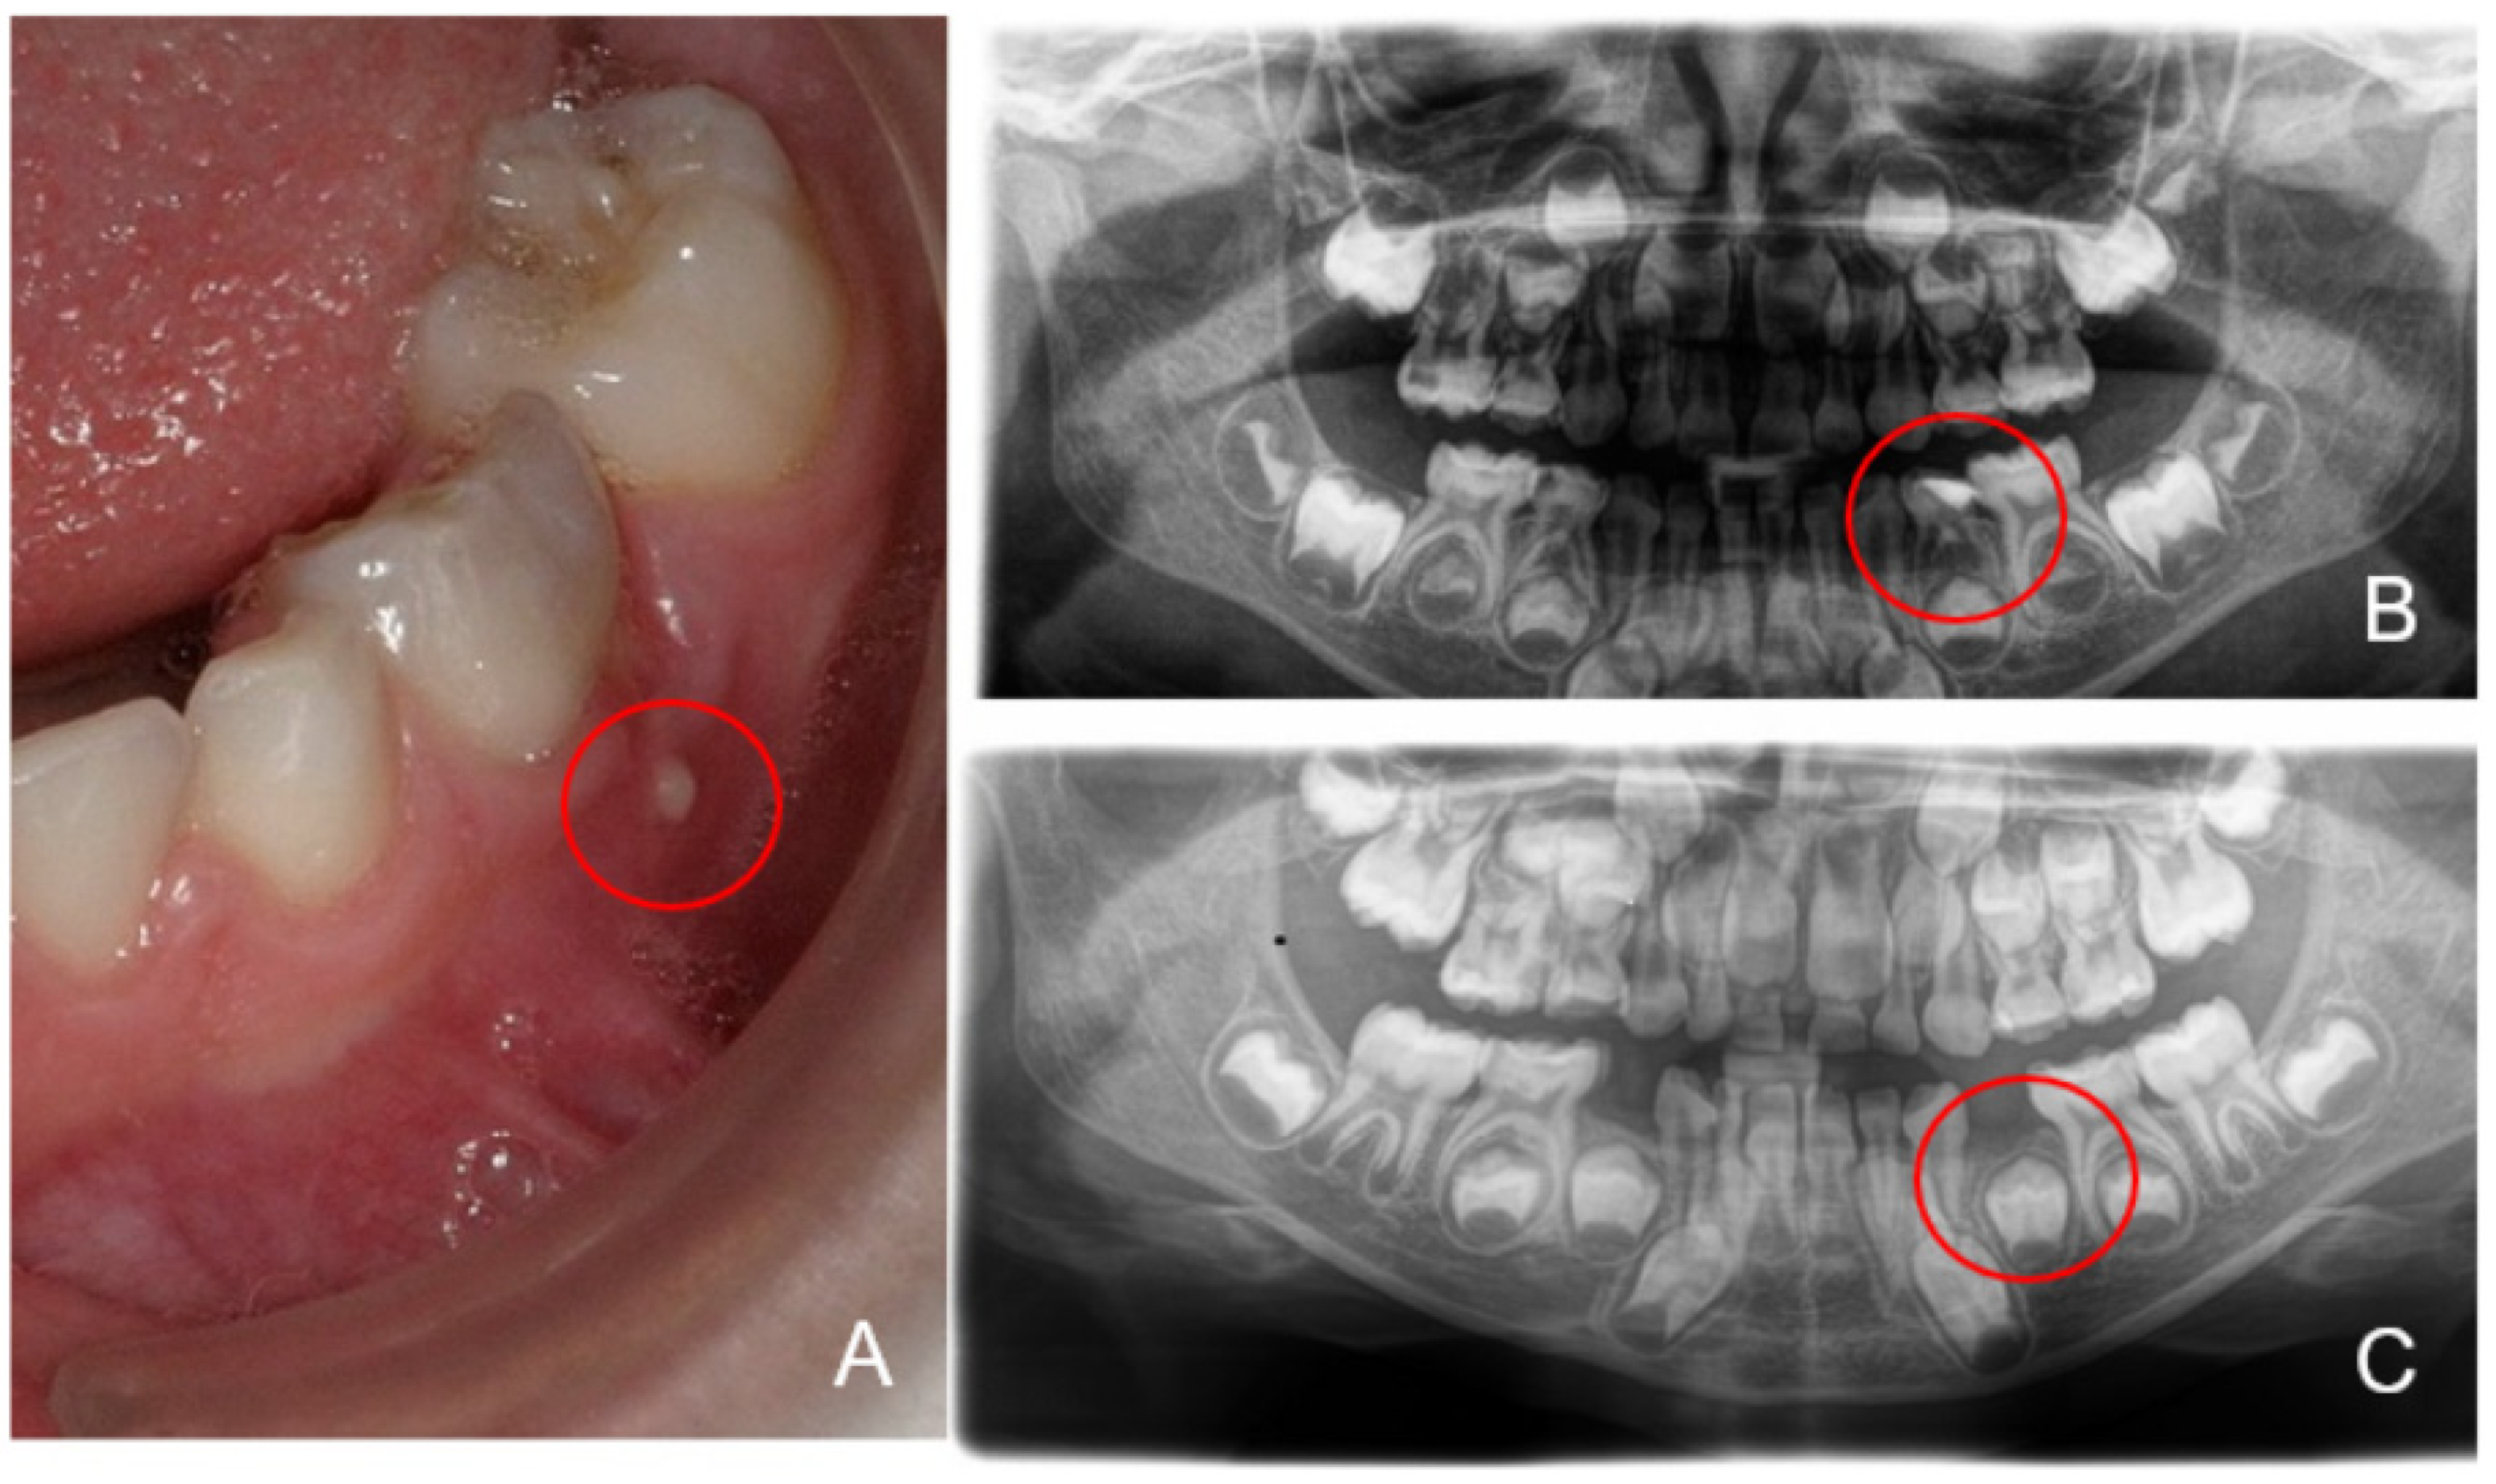

2.1. Dental Examination and Sampling